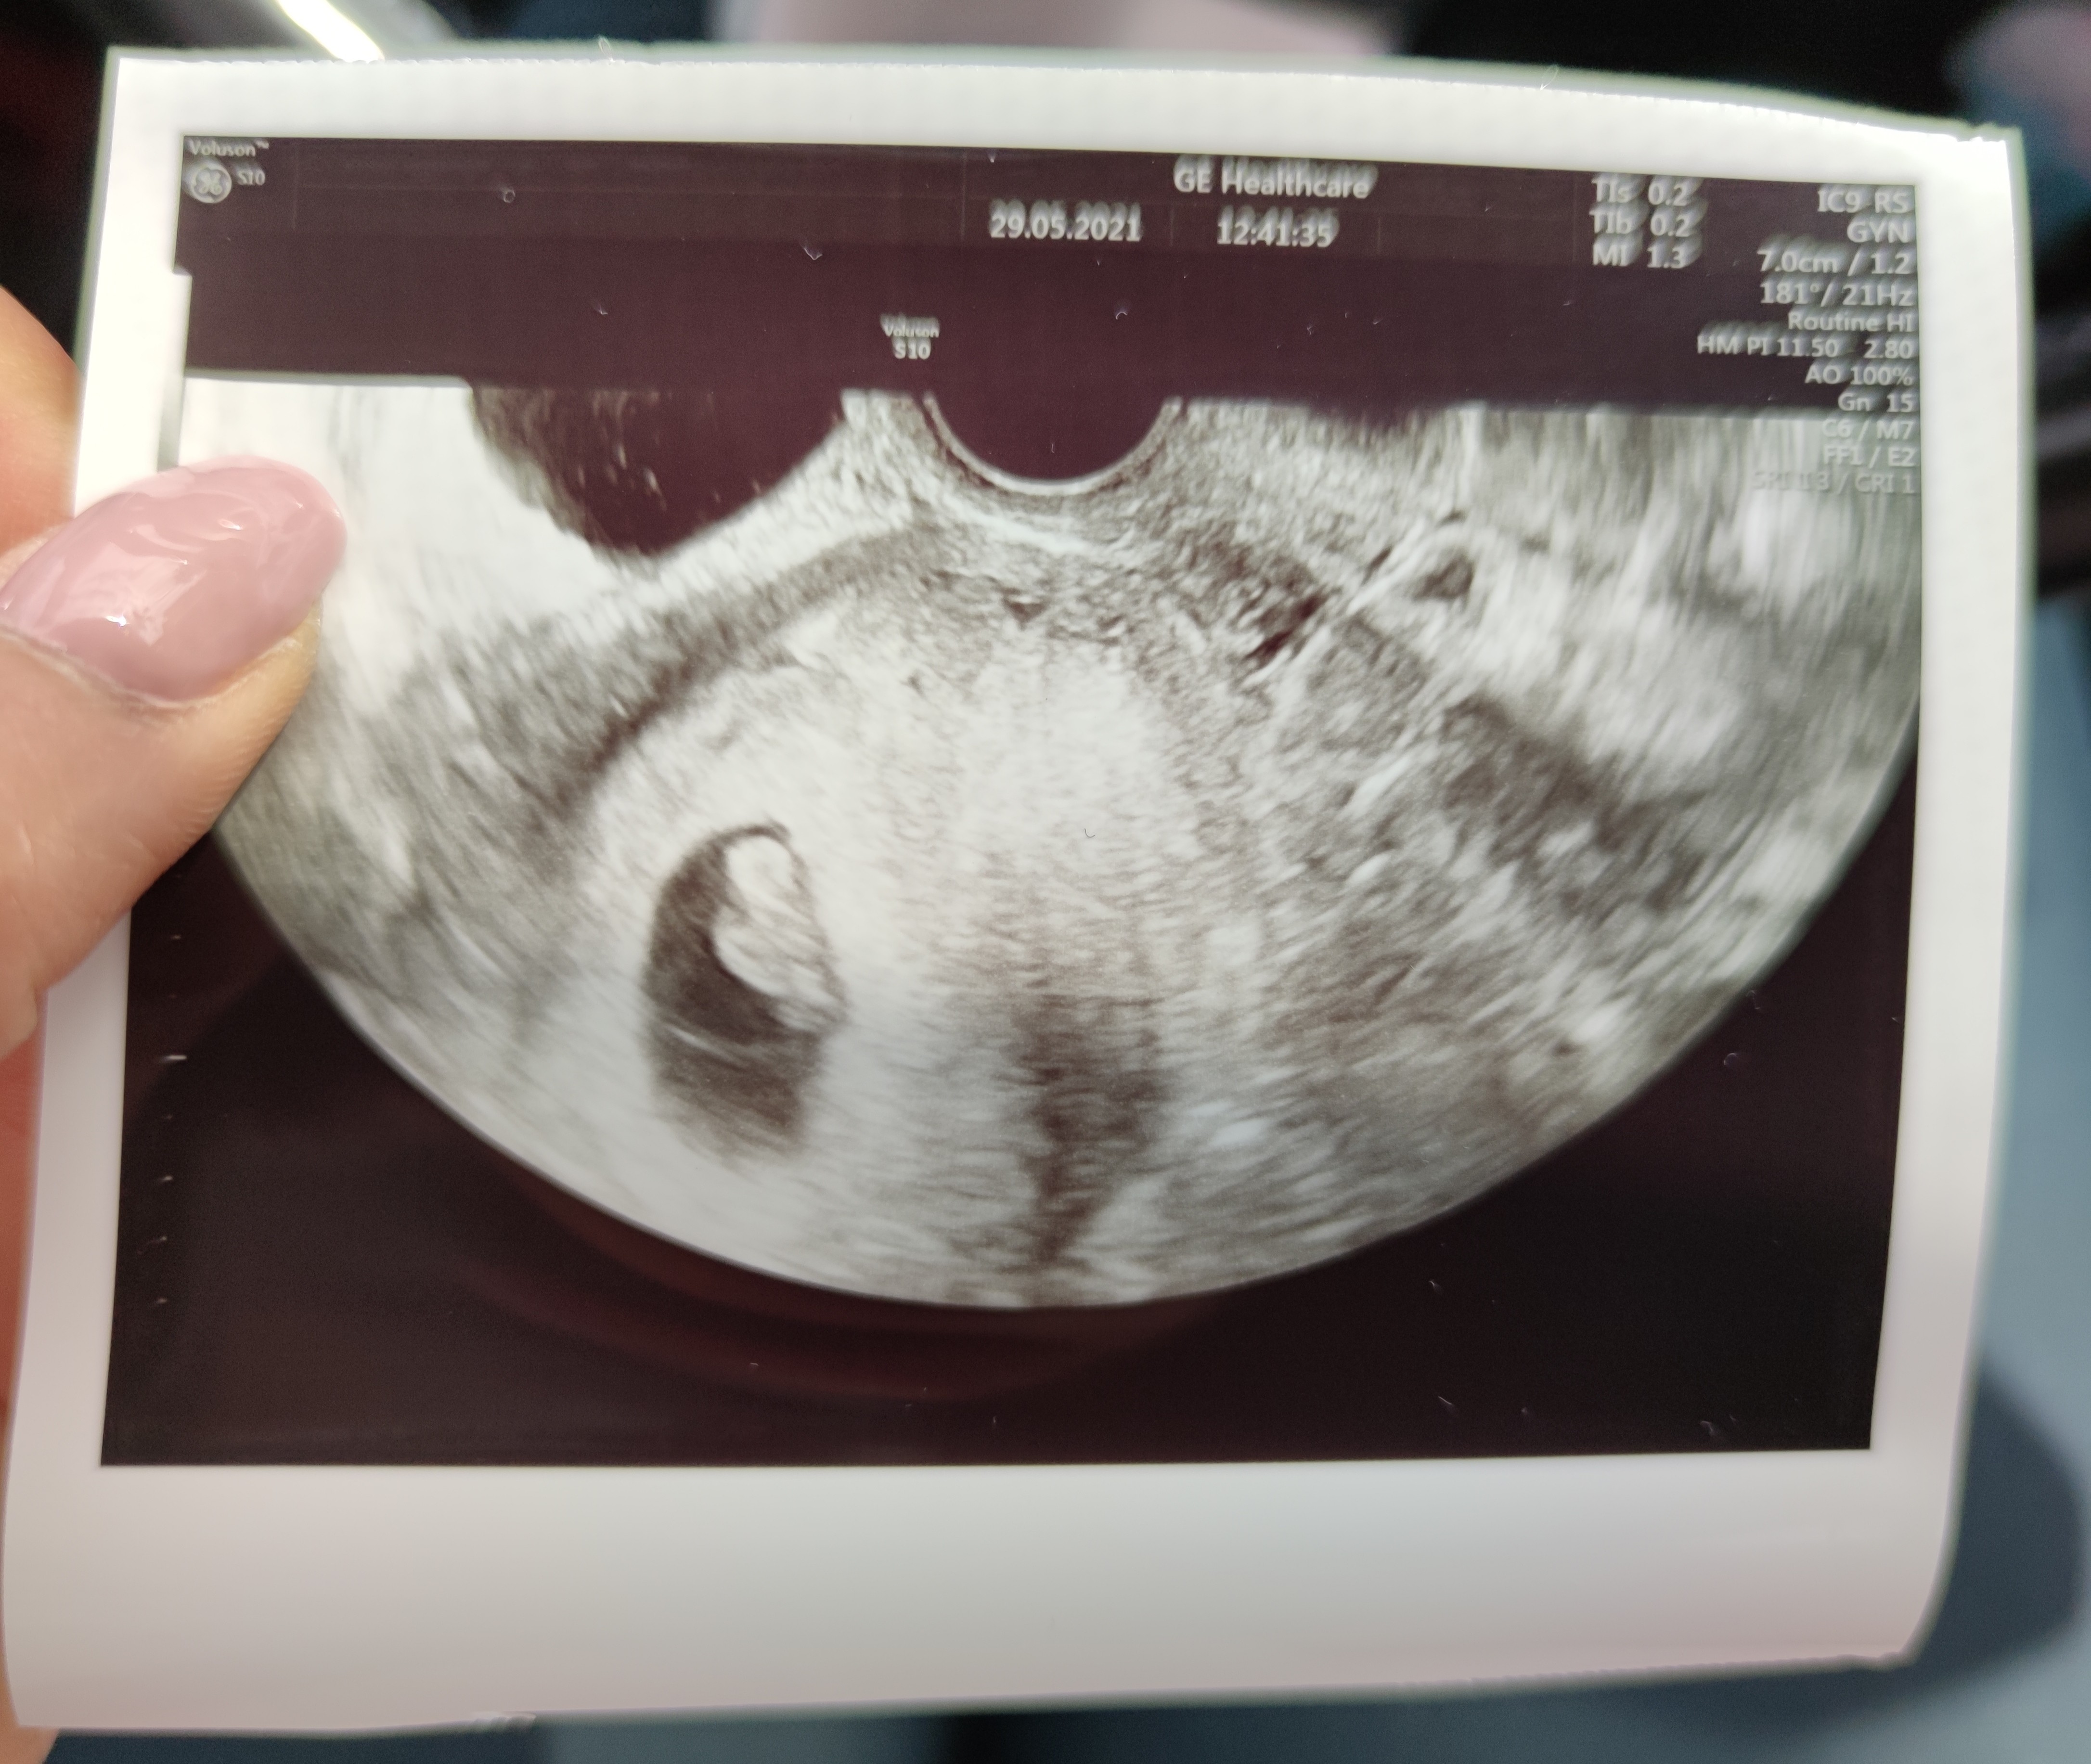

Wydaje mi się, że tę ciąże znoszę dużo gorzej teraz po 30stce niz z córcią 8 lat temu. Pamietam że rzygałam jak kot ale latałam wszędzie. Teraz ledwo co się doczołgam do lekarza i już marze o łóżku..